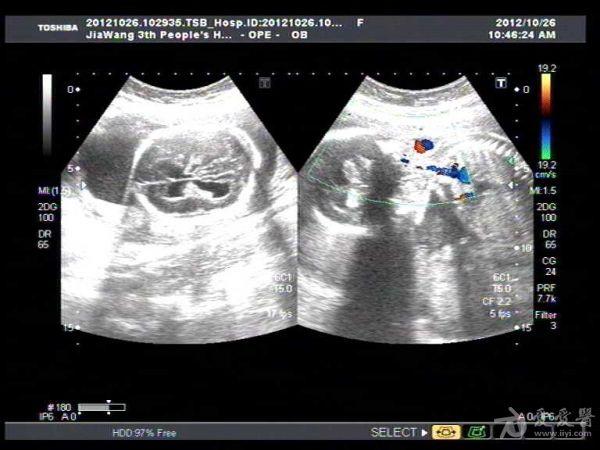

胎儿脑积水一例

此孕妇22岁,于孕六月来我院产检,可见胎儿侧脑室扩张积液约1.4Cm,遂告知小孩脑

积水,此孕妇接着去我们当地三甲医院检查,也被告知胎儿脑积水,建议引产。

此孕妇听信家人说吃核桃能补脑,吃了两个月核桃来来复查,脑积水更明显。